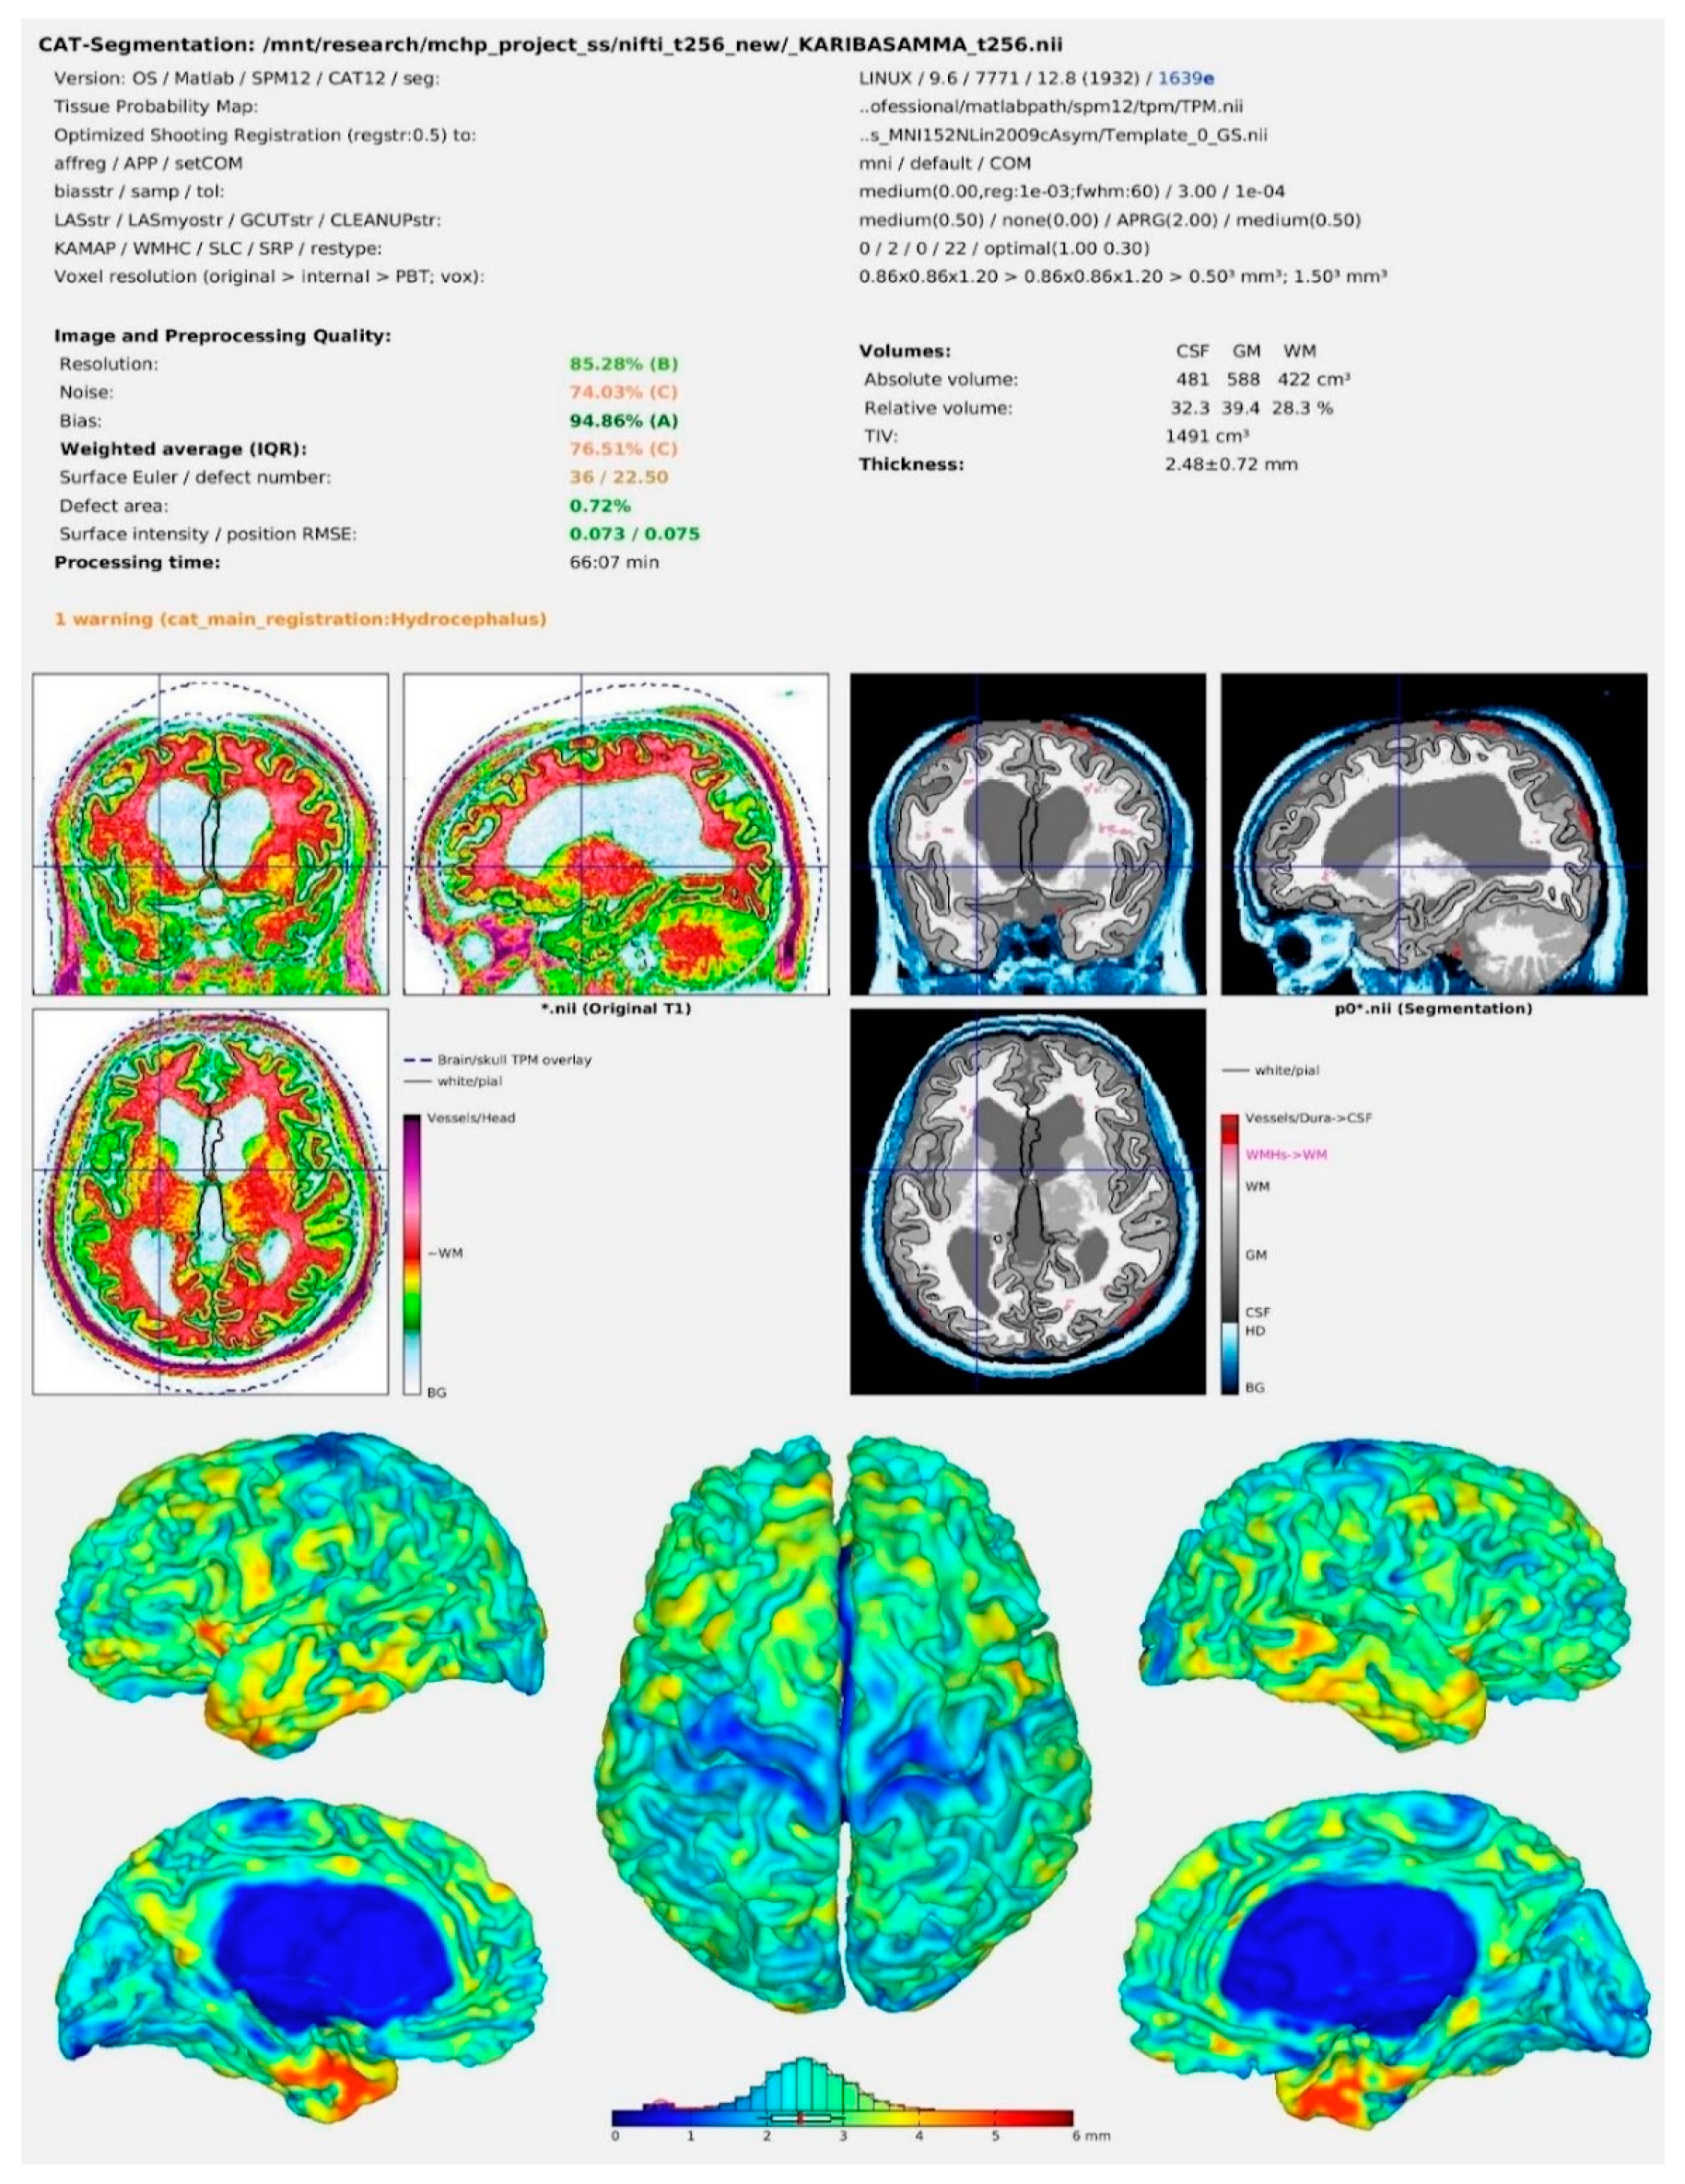

The pre-processing steps were carried out with the help of CAT12 (computational anatomy toolbox—version 12.8) (RRID: SCR_019184 accessed on 1 March 2022 installed in the SPM12 (statistical parametric mapping—version 12 (Version7771)) software (RRID:SCR_007037) accessed on 15 April 2022 (ftp:/ftp.fil.ion.ucl.ac.uk/spm.) MATLAB (version R2019a) (RRID:SCR_001622) was used as a common platform for these programs. MRI Convert version 2.1.0 accessed on 1 March 2022 was used to convert all DICOM images to NIfTi format. During the pre-processing steps, all the images were normalized and segmented. Furthermore, all pre-processed images were subjugated to a sample homogeneity test and a careful evaluation for image quality. Images with a weighted overall image quality of more than 70% were chosen for further examination. Furthermore, using the estimate option in the software, values for volumes of GM, WM, cerebrospinal fluid (CSF), and total intracranial volume (TIV) were calculated from each image using the estimate option in the CAT12 software. GMVs of 170 brain areas based on the automated anatomical labeling (AAL-3) atlas were acquired for each participant during pre-processing steps using the CAT12 tool in expert mode. The prime page has been shown in Figure 1.

Figure 1.

CAT12 result output image after pre-processing of the MRI scans.